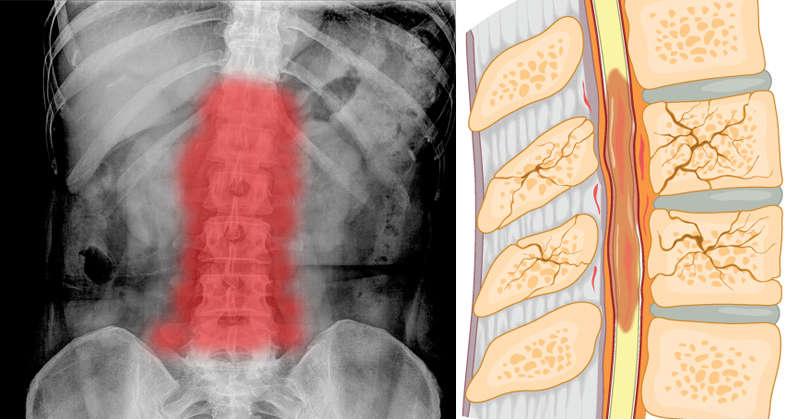

“Given the limited number of successful therapies available today for repairing lost tissues, we need to look to animals like zebrafish for new clues about how to stimulate regeneration.” When the zebrafish’s severed spinal cord undergoes regeneration, a bridge forms, literally.

The first cells extend projections into a distance tens of times their own length and connect across a wide gulf of the injury.

Nerve cells follow and by eight weeks, new nerve tissue fill the gap and the animals fully reverse their severe paralysis. To understand what molecules were potentially responsible for this remarkable process, the scientists conducted a molecular fishing expedition of sorts, searching for all of the genes whose activity abruptly changed after spinal cord injury. Of dozens of genes strongly activated by injury, seven coded for proteins that are secreted from cells.